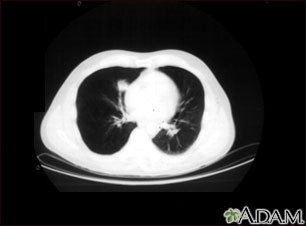

A chest CT (computed tomography) scan is an imaging method that uses x-rays to create cross-sectional pictures of the chest and upper abdomen.

A CT scan quickly creates detailed pictures of the body. The test may be used to get a better view of the structures inside the chest. A CT scan is one of the best ways of looking at soft tissues such as the heart and lungs.